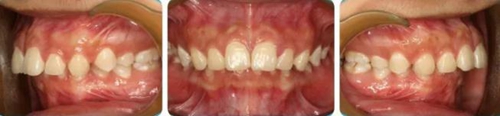

李某,女性,18歲,咬合不良要求矯治。

正面觀雙側(cè)面型基本對稱,側(cè)面觀上頜凸、下頜后縮,頦唇溝深。

恒牙列,上下牙列中線對齊,前牙深覆合、深覆蓋均為Ⅲ°。雙側(cè)磨牙、尖牙為Ⅱ類遠中關(guān)系,A4C4、B4D4正鎖合。

(1)安氏Ⅱ類1分類錯合;

(2)A4C4,B4D4正鎖合;

(3)前牙重度深覆合、深覆蓋。